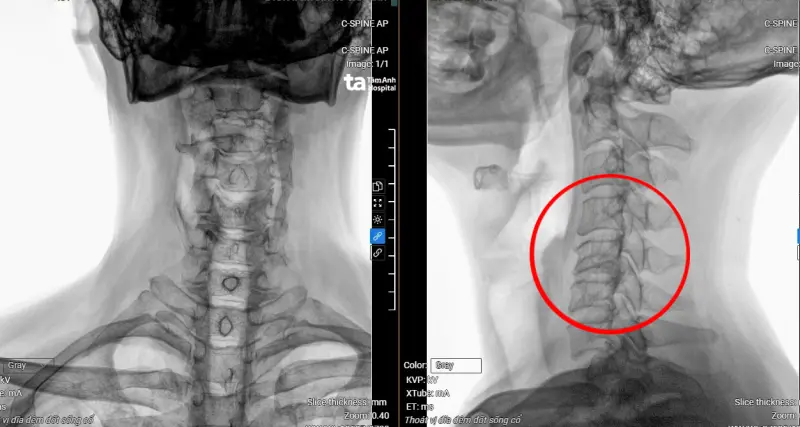

ThS.BS.CKI Vũ Đức Thắng, khoa Cột sống Trung tâm chấn thương chỉnh hình Bệnh viện Đa khoa Tâm Anh TP Hồ Chí Minh cho biết, qua kết quả chụp MRI 3 Tesla cho thấy bệnh nhân An bị thoát vị đĩa đệm cột sống cổ nặng từ C3 đến C7, gù cột sống cổ, chèn ép làm tổn thương tủy C5, C6 (vị trí đốt sống cổ thứ 5 và thứ 6). Ngoài ra, cột sống thắt lưng của anh cũng bị thoát vị và chèn ép thần kinh khá nặng ở tầng L4, L5 (vị trí đốt sống lưng thứ 4 và thứ 5).

- Hình bìa: Phim chụp MRI hiển thị vị trí đốt sống cổ bị thoát vị, tổn thương tủy. Ảnh: BV